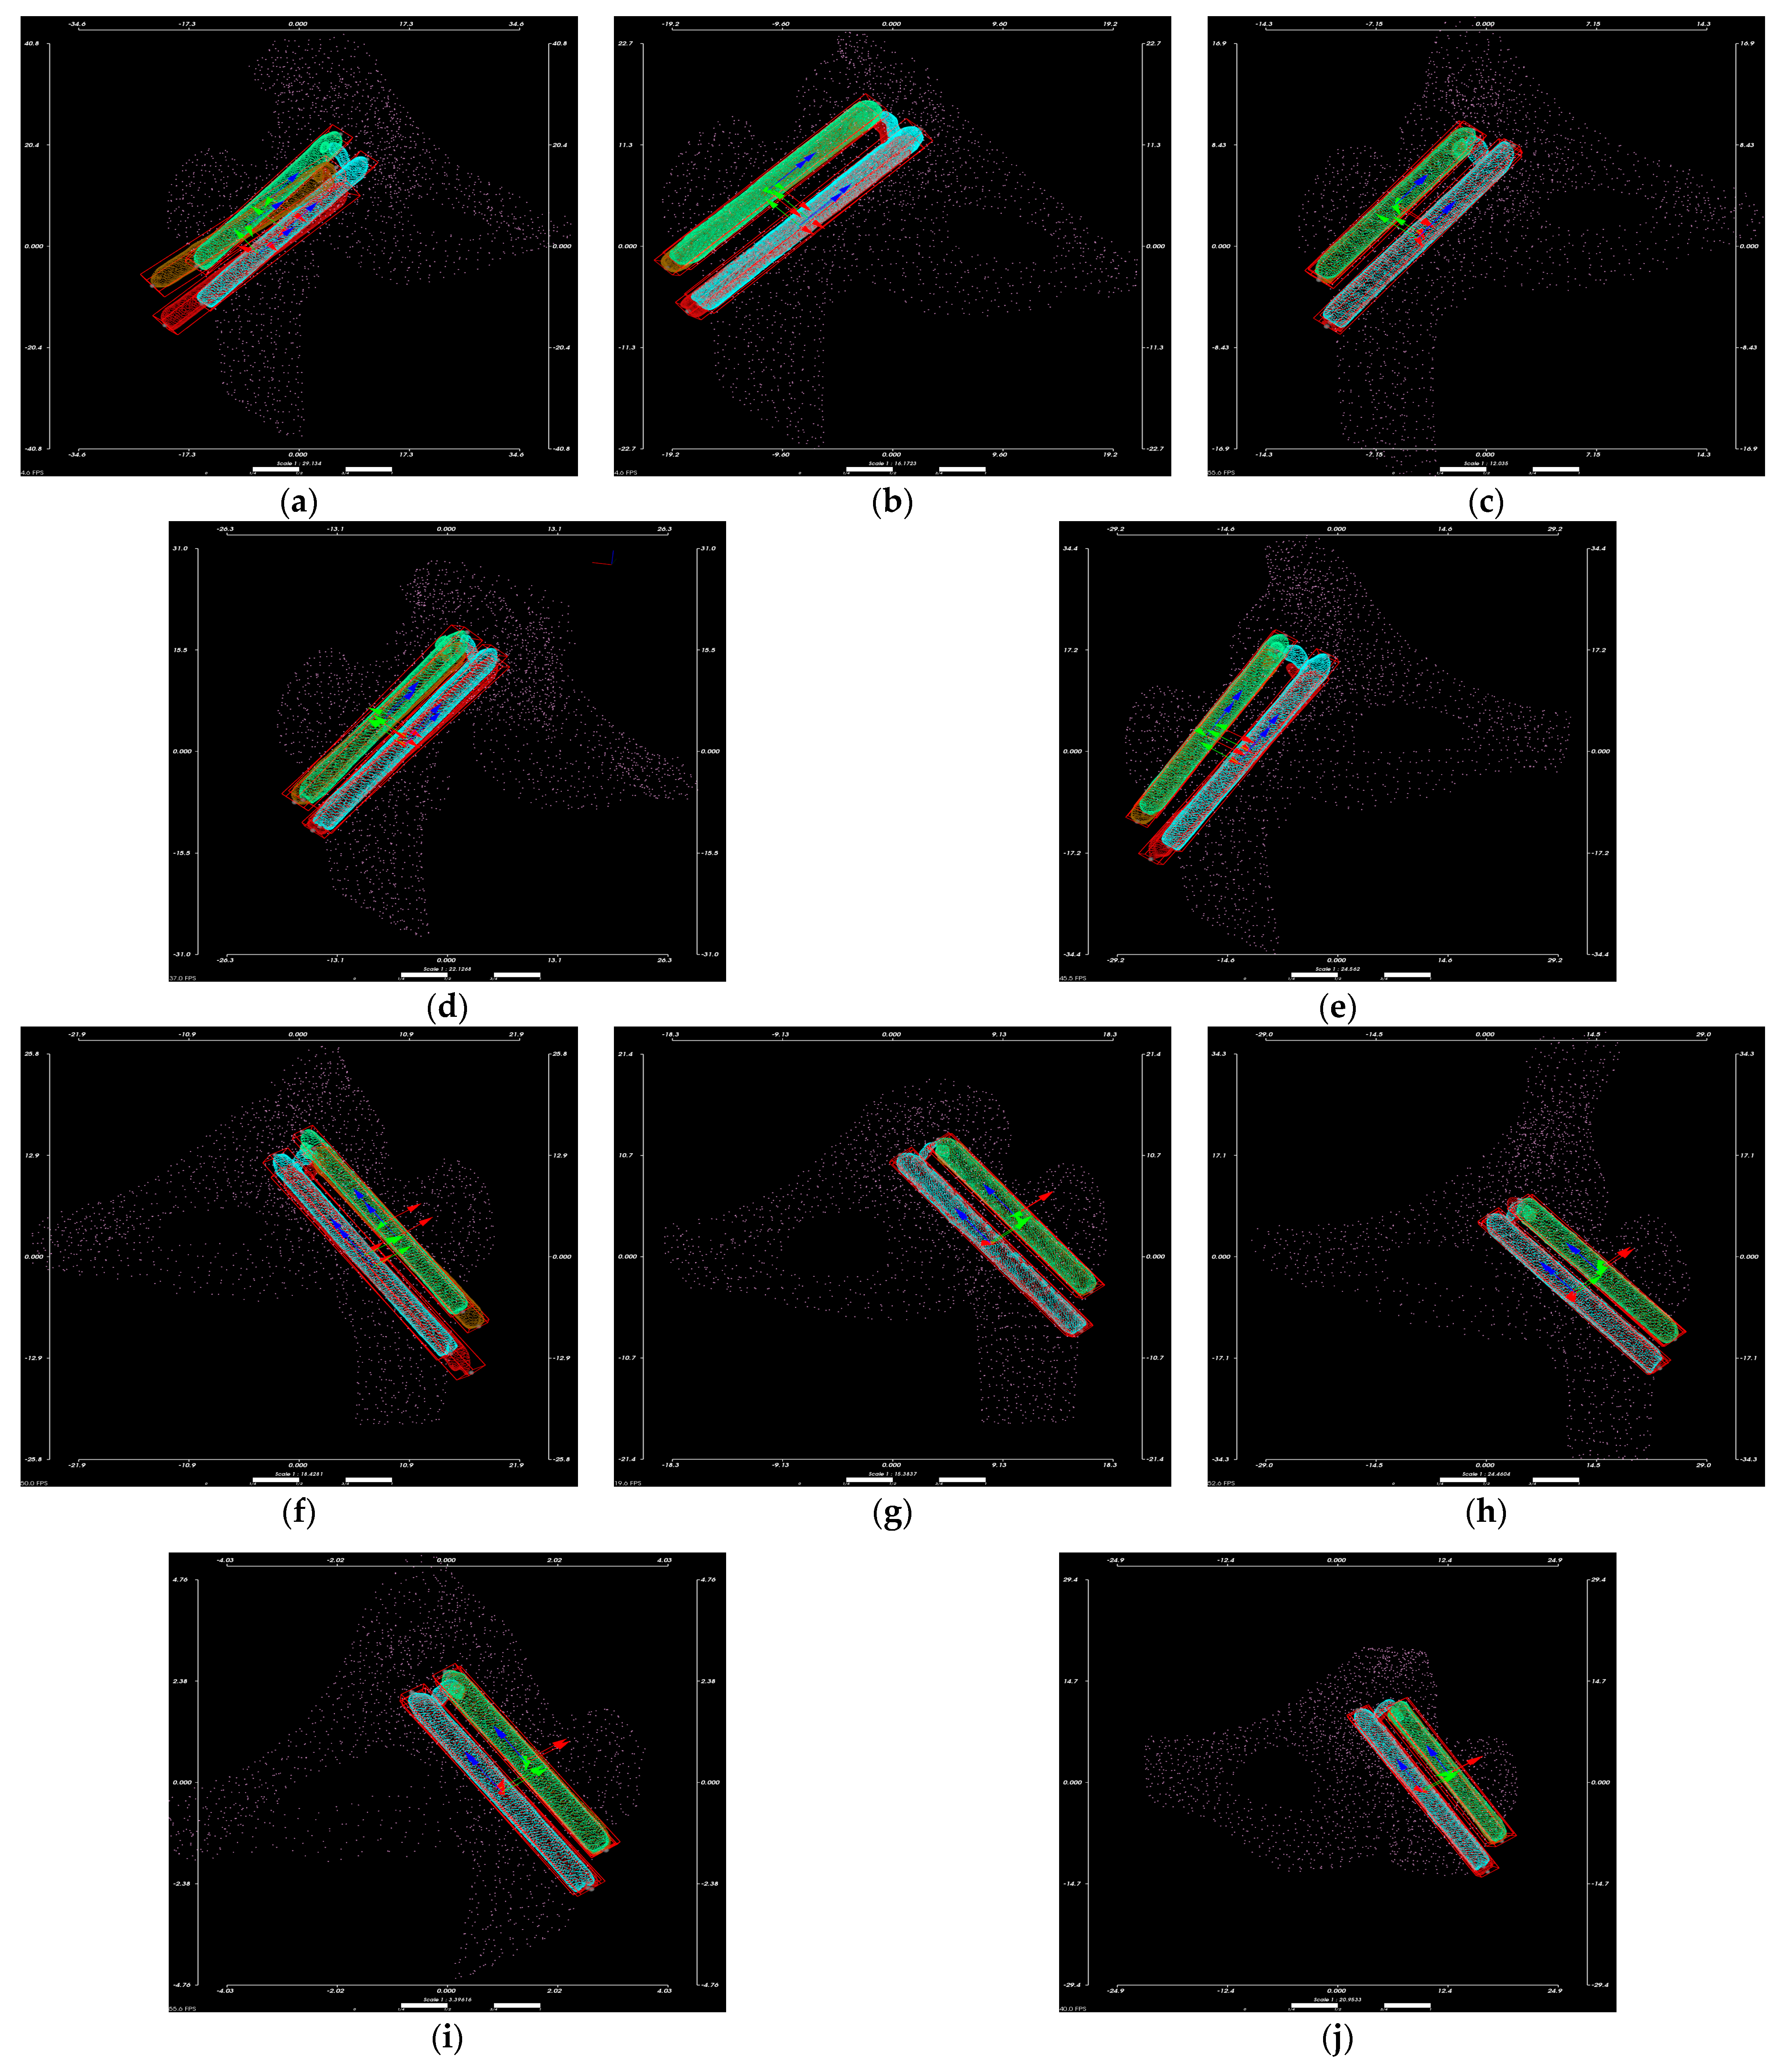

The fine-aligned CT images were transformed by 3D reconstruction to obtain the point cloud data, as in Figure 20.

Figure 20.

Hansson pins point clouds: from (a–e) is the Hansson pins point clouds used for the left femur; from (f–j) is the Hansson pins point clouds used for the right femur.

To ensure that the 3D point cloud data can represent the actual size and accurate displacement calculation of Hansson pins, we compared the pins’ actual length with the measured length of the point cloud data, and the results are reported in Table 4. Each case contains two sets of CT images, fixed images, and floating images; all the results are presented. The error between the length of the pins calculated by the point cloud and the actual length is within 2 mm.

Table 4.

Comparison of the actual length of Hansson pins with the point cloud data.